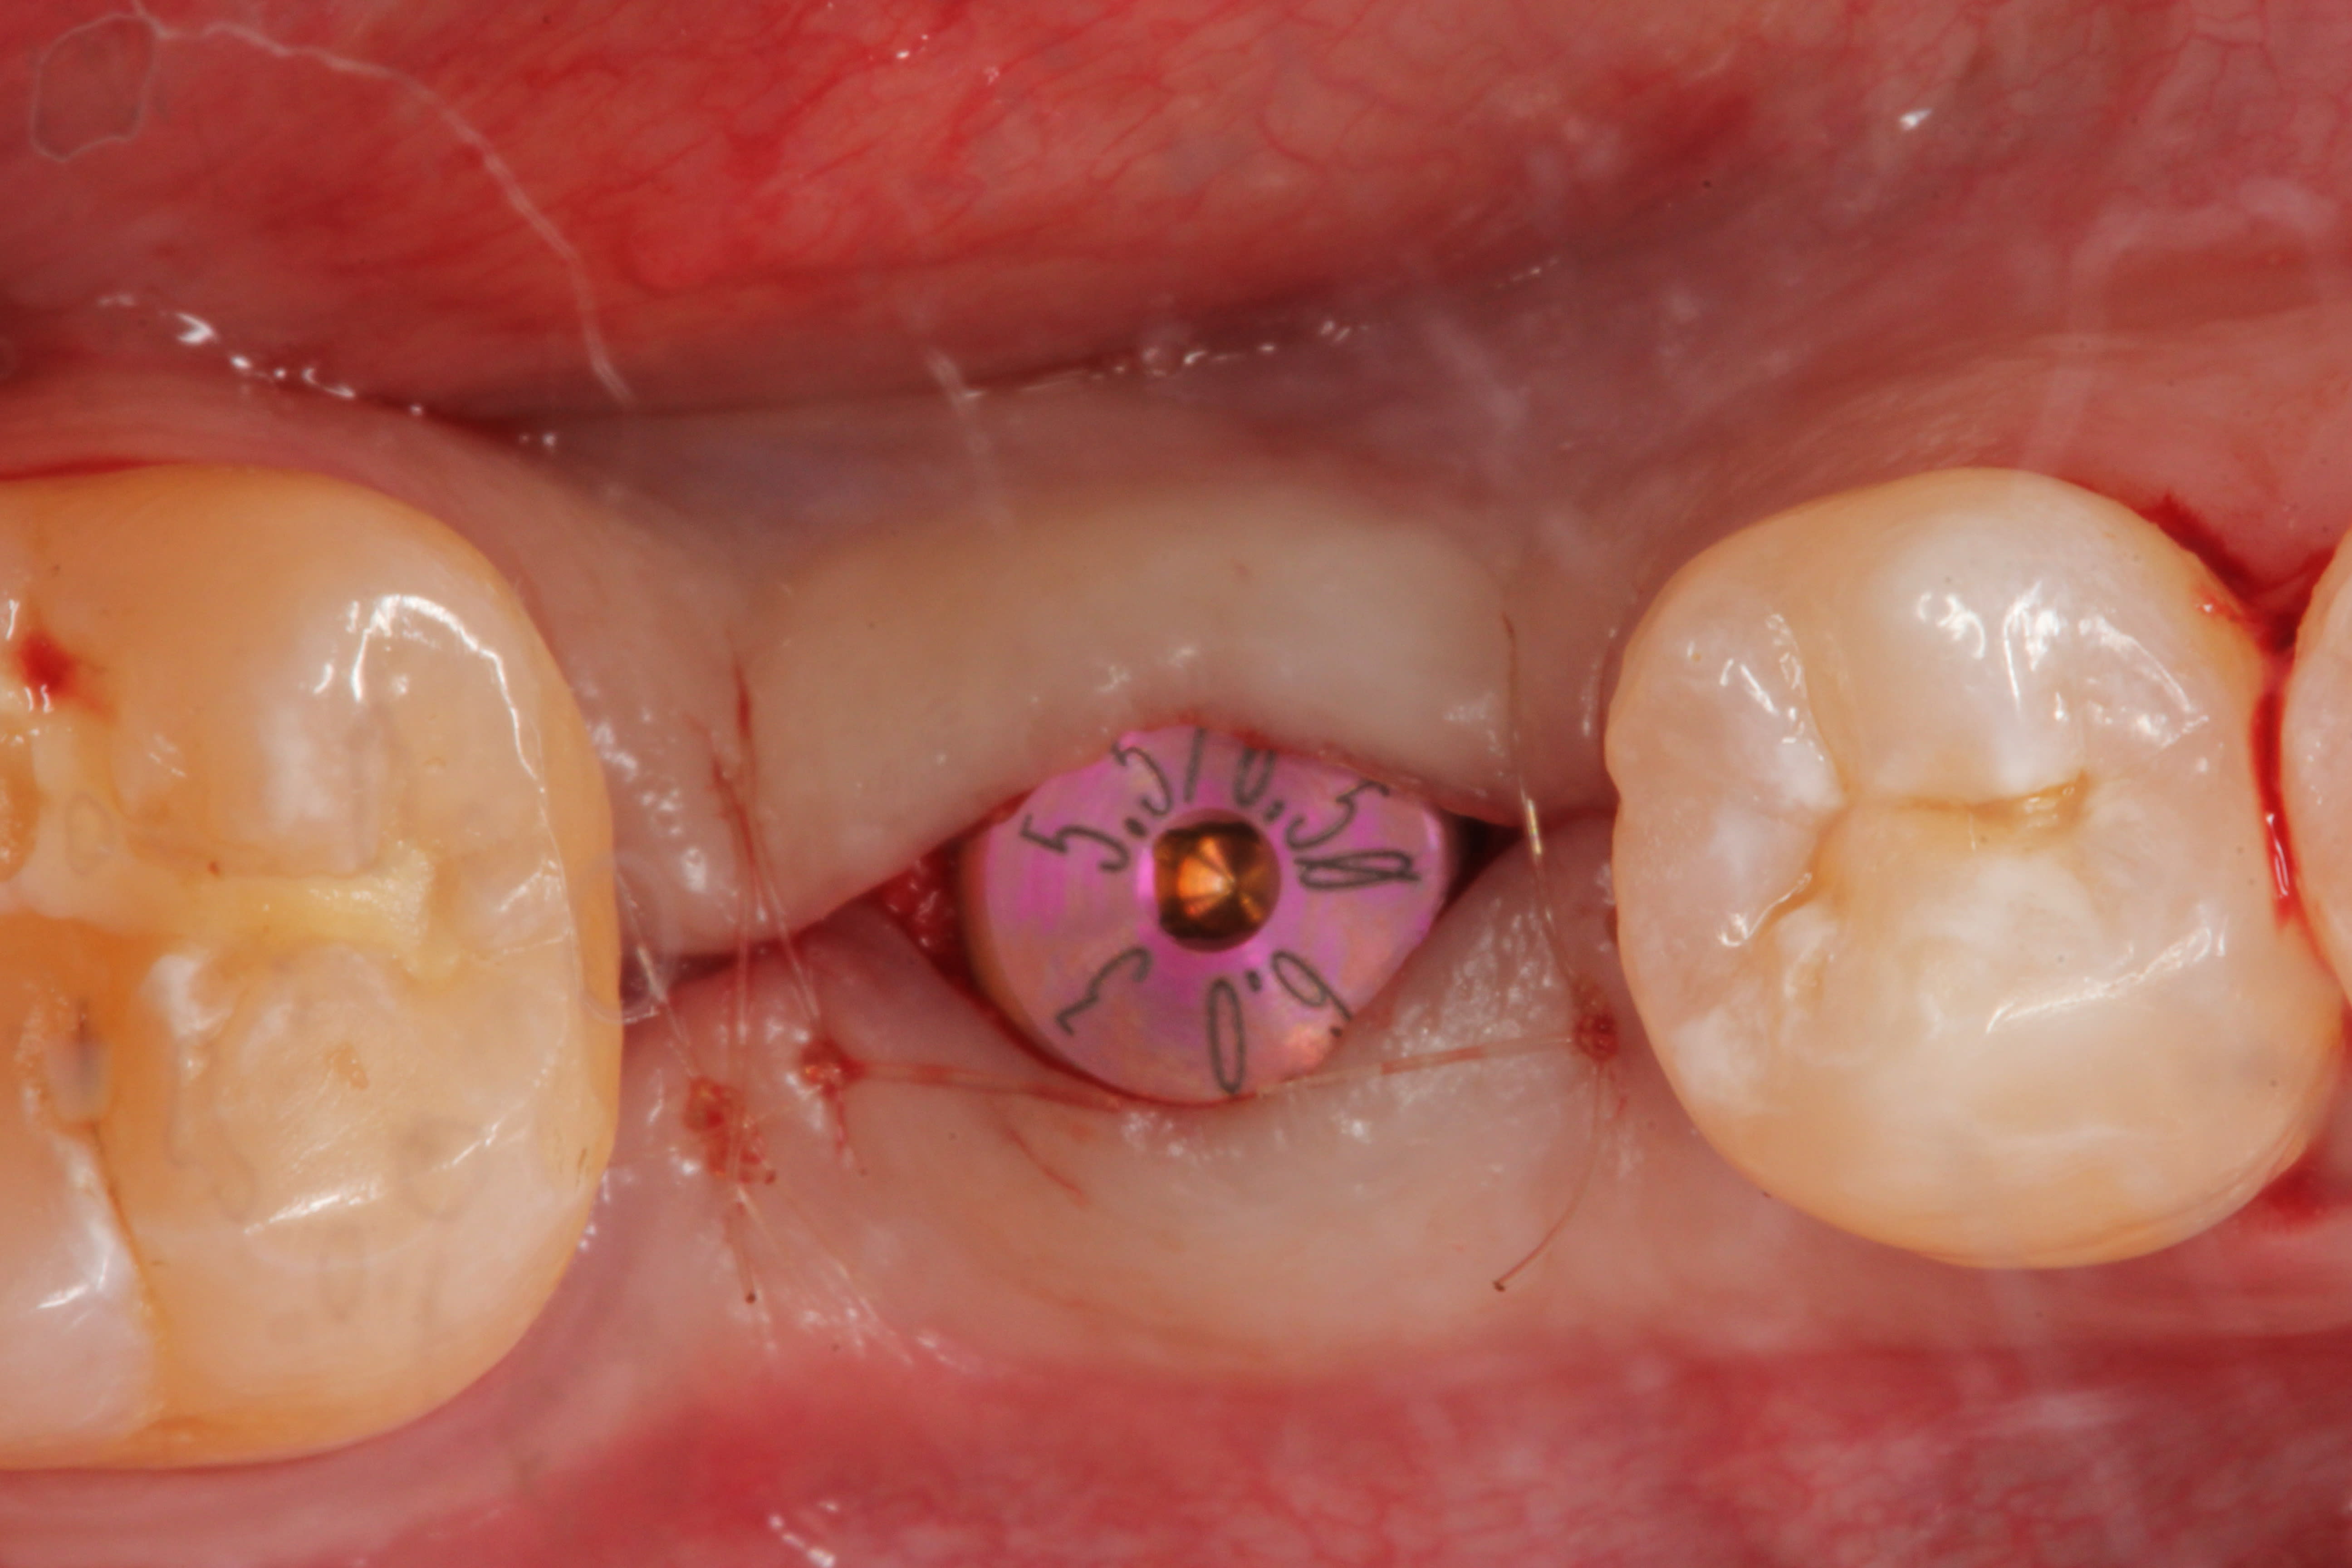

In February 2012 the patient enrolled in the multicenter study, and a 5.5-mm x 11.5-mm implant (Genesis) was placed (Figure 42). Minor contour bone grafting of the site was also performed using autogenous bone directly against the buccal cortex and layered thereafter with a corticocancellous allograft (Puros) along the lateral aspect of the implant. This was done to increase the peri-implant bone and mucosal thickness (existing bone thickness was <1 mm on the buccal aspect) in an effort to improve parameters that would reduce the incidence of recession over the long term.

The 5.5-mm implant platform was used to accommodate the high occlusal load typically associated with the molar area and to optimize the esthetic emergence profile of the final restoration, neither of which would have been feasible with a narrower implant, even in the presence of more robust socket augmentation. A healing abutment was placed (Figure 43).

A high implant stability quotient (Osstell® ISQ = 80) (Osstell, www.osstell.com) and insertion torque values >50 Ncm allowed the prosthetic phase to begin in April 2012 (Visit 3). Figure 44 shows the periapical radiograph at Visit 3; Figure 45 shows good healing and tissue tone at this visit as well.